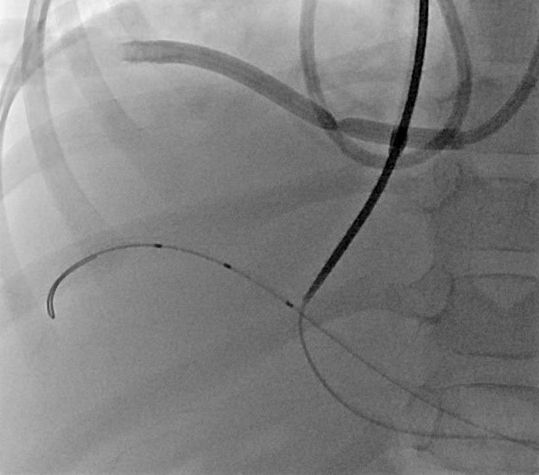

7 jähriger Junge mit Kurzdarmsyndrom und Leberzirrhose

Als Folgen des Pfortaderhochdrucks war die Milz vergrößert (Splenomegalie) und es traten Krampfadern der Speiseröhre (Ösophagusvarizen) auf. Um den Hochdruck zu entlasten wurde ein TIPS angelegt. Dazu wird aus der rechten Lebervene (A) mit einer speziellen Nadel ein Pfortaderast punktiert (B). Anschließend wird die Pfortader mit einem Draht sondiert (C) und die geschaffene Verbindung mit einem Ballon aufgedehnt und anschließend mittels Gefäßstütze (Stent) geschient (D). Durch diese künstliche Verbindung kann das Pfortadersytem deutlich druckentlastet werden.